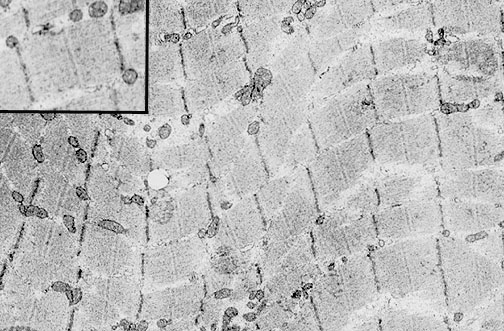

| In this electron micrograph of normal skeletal muscle, myofibrils are present, surrounded by an endomysium with vascular supply and peripheral nuclei. Each myofibril is composed of interdigitating thin actin and thick myosin filaments. The inset at the upper left demonstrates a single sarcomere with thin actin and thick myosin filaments that interdigitate, bounded on each side by a dark Z disc, and a central M line. |